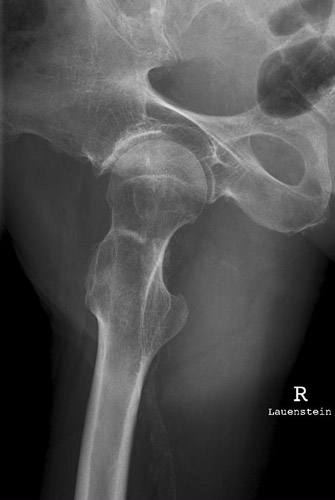

Lauenstein

Fehler

Der distale Schenkelhalsteil wird durch den Trochanter major verdeckt, wobei aber der mediale gelegene Abschnitt relativ frei ist. Außerdem ragt der Trochanter minor besonders markant und in ganzer Ausdehnung hervor und projiziert sich weit distal vom Trochanter major. Diese Fehleinstellung kommt vor allem bei Menschen mit schweren arthrotischen Knochenwülsten (Coxarthrosis deformans) am Hüftgelenk vor.

Abhilfe

Der Patient konnte zwar seinen Oberschenkel abspreizen, aber offenbar nur ungenügend; er drehte daher das Bein stark nach außen, was den Trochanter minor auf dem Bild mächtig hervorragen ließ.